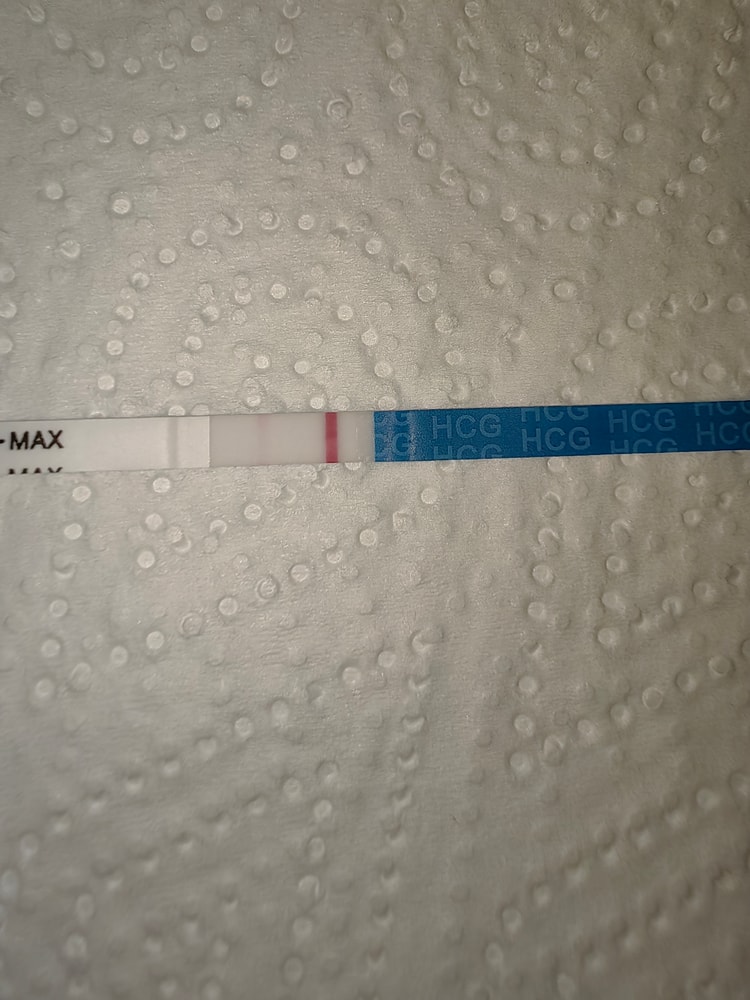

Вчера клиаблю непонятно что мне нарисовал, поэтому сегодня я снова сделала тест))

фоткала под разными освещениями. Очень уж хочется, чтобы кто-то кроме меня тоже увидел полоску🤣🤣 фотки, где теста два - верхний это вчерашний утренний, а нижний сегодняшний. Видите ли вы что-нибудь?🥺

На нижнем вижу //